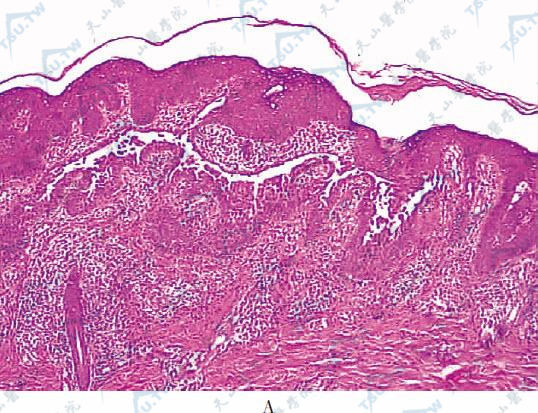

1970年Grover首先报道本病。因此又名格罗弗病(Grover's disease)、丘疹性棘层松解性皮病(papular acantholytic dermatosis)。主要侵犯中年或老年人的躯干部位,典型皮损为瘙痒性